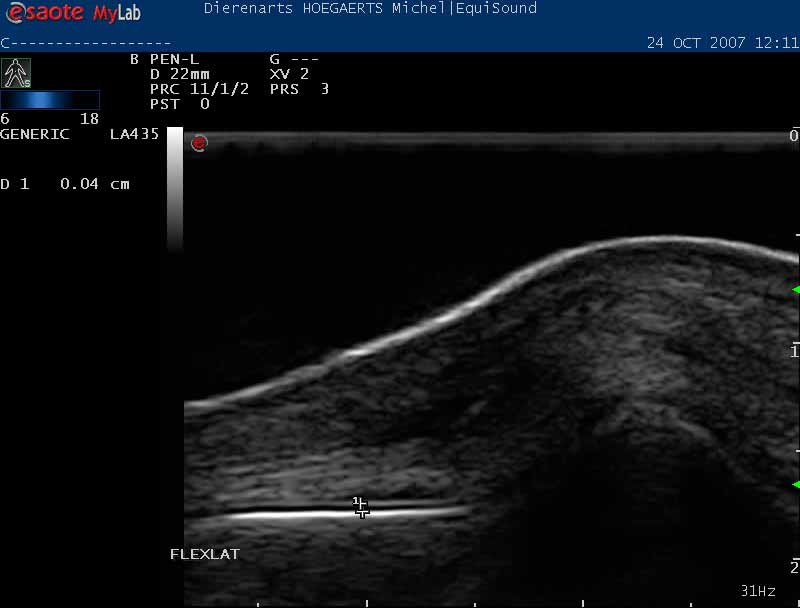

Onderzoek van peesblessures

Peesletsels (tendinitis of tendinose) ter hoogte van de strek- en buigpezen van voor- en achterbenen komen frequent voor. Het zijn de zwakke schakels tussen de spieren en hun aanhechting op het bot.

Als de pezen gezwollen, warm en pijnlijk zijn, is het belangrijk om ze met een echografie te onderzoeken. Zo kunnen we nagaan hoe groot en hoe uitgebreid het letsel is en een gepaste behandeling of revalidatie voorstellen. Het doel is om het herstelweefsel zo optimaal mogelijk te maken en uw paard zo snel mogelijk weer aan het werk te krijgen.